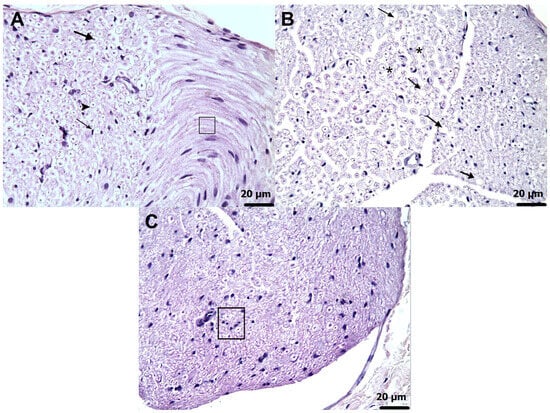

Background: Amiodarone is a widely used class III antiarrhythmic agent, but its use can lead to peripheral neuropathy mediated by mitochondrial dysfunction, oxidative stress, and neuroinflammatory injury, while effective preventive options remain limited. Agents that support mitochondrial energy metabolism, sustain redox balance, and [...] Read more.

Background: Amiodarone is a widely used class III antiarrhythmic agent, but its use can lead to peripheral neuropathy mediated by mitochondrial dysfunction, oxidative stress, and neuroinflammatory injury, while effective preventive options remain limited. Agents that support mitochondrial energy metabolism, sustain redox balance, and modulate inflammation, including adenosine triphosphate (ATP), melatonin, and thiamine pyrophosphate (TPP), may counteract these mechanisms; however, their relative neuroprotective potential in amiodarone-induced neuropathy remains unclear. This study aimed to comparatively evaluate the effects of ATP, melatonin, and TPP on amiodarone-induced peripheral neuropathy and neuropathic pain in rats. Methods: Thirty male albino Wistar rats were assigned to five groups: healthy; amiodarone (50 mg/kg/orally); amiodarone + ATP (5 mg/kg/intraperitoneally); amiodarone + melatonin (10 mg/kg/orally); or amiodarone + TPP (20 mg/kg/intraperitoneally). Treatments were given once daily for 14 days. Oxidative stress indices (malondialdehyde (MDA), total glutathione (tGSH), superoxide dismutase (SOD), catalase (CAT)) and proinflammatory cytokines (tumor necrosis factor-alpha (TNF-α), interleukin-1 Beta (IL-1β), interleukin-6 (IL-6)) were quantified in sciatic nerve by Enzyme-Linked Immunosorbent Assay (ELISA). Paw withdrawal thresholds were measured with the Randall-Selitto test before and after treatment. Histopathology was performed using Hematoxylin-eosin staining. Results: Amiodarone exposure resulted in pronounced elevations in MDA and proinflammatory cytokine levels, accompanied by significant reductions in tGSH, SOD, CAT activities, and paw withdrawal thresholds. ATP, melatonin and TPP ameliorated these alterations to varying degrees. Among them, TPP provided the most robust antioxidant and anti-inflammatory effects, followed by ATP and melatonin. Histopathological examination confirmed most severe axonal degeneration, interstitial edema and Schwann cell proliferation in the amiodarone group, with substantial amelioration in the TPP-treated rats. Conclusions: Amiodarone induces neuropathic pain through oxidative and inflammatory injury to peripheral nerves. TPP exhibited superior neuroprotective efficacy compared with ATP and melatonin, highlighting its potential as a candidate therapeutic agent for amiodarone-related neuropathy. Further clinical research is warranted to support translational application of these findings. Full article

(This article belongs to the Special Issue Advanced Research in Neuroprotection)